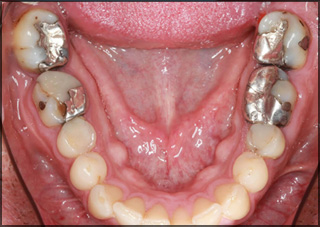

Do I need to get my cavities filled?

Early decay doesn't always mean you need a filling. In fact, the decay often can be reversed. A tooth starts to decay because acid in your mouth causes minerals to leach out of the enamel, and the enamel breaks down. If there's no cavity and no pain, the tooth can fix itself.

Which filling is best for teeth?

Today, several dental filling materials are available. Teeth can be filled with gold; porcelain; silver amalgam (which consists of mercury mixed with silver, tin, zinc, and copper); or tooth-colored, plastic, and materials called composite resin fillings.

How long do composite fillings last?

With more durable resin material available for only a decade, resins haven't stood the test of time in teeth where grinding and chewing result in heavy wear; by contrast, the durability of amalgam fillings is well documented the average life span of amalgams is 8 to 10 years, but many last 20 years or more

What is in a temporary filling?

If your dentist is filling a cavity, you could get a temporary filling before you get the permanent one. ... A temporary filling is a filling that has been placed to seal a tooth until a final filling can be placed. It is generally a soft material that has been placed into the tooth to fill a broken area or area of decay.